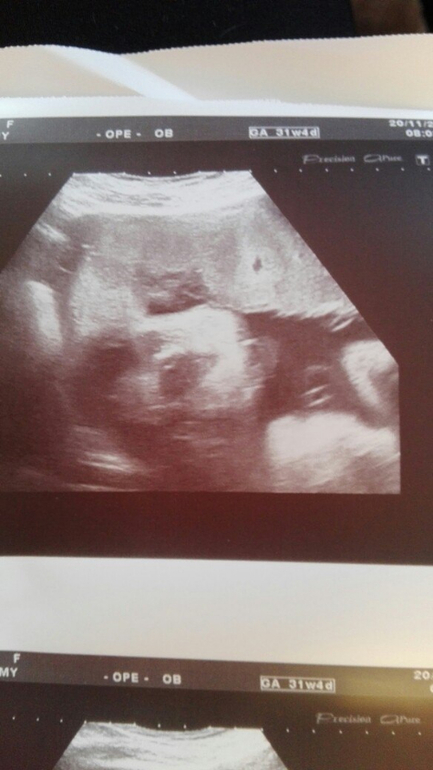

а это четкий наш девочковый пирожок))) чтоб сомнений у папы не осталось))))